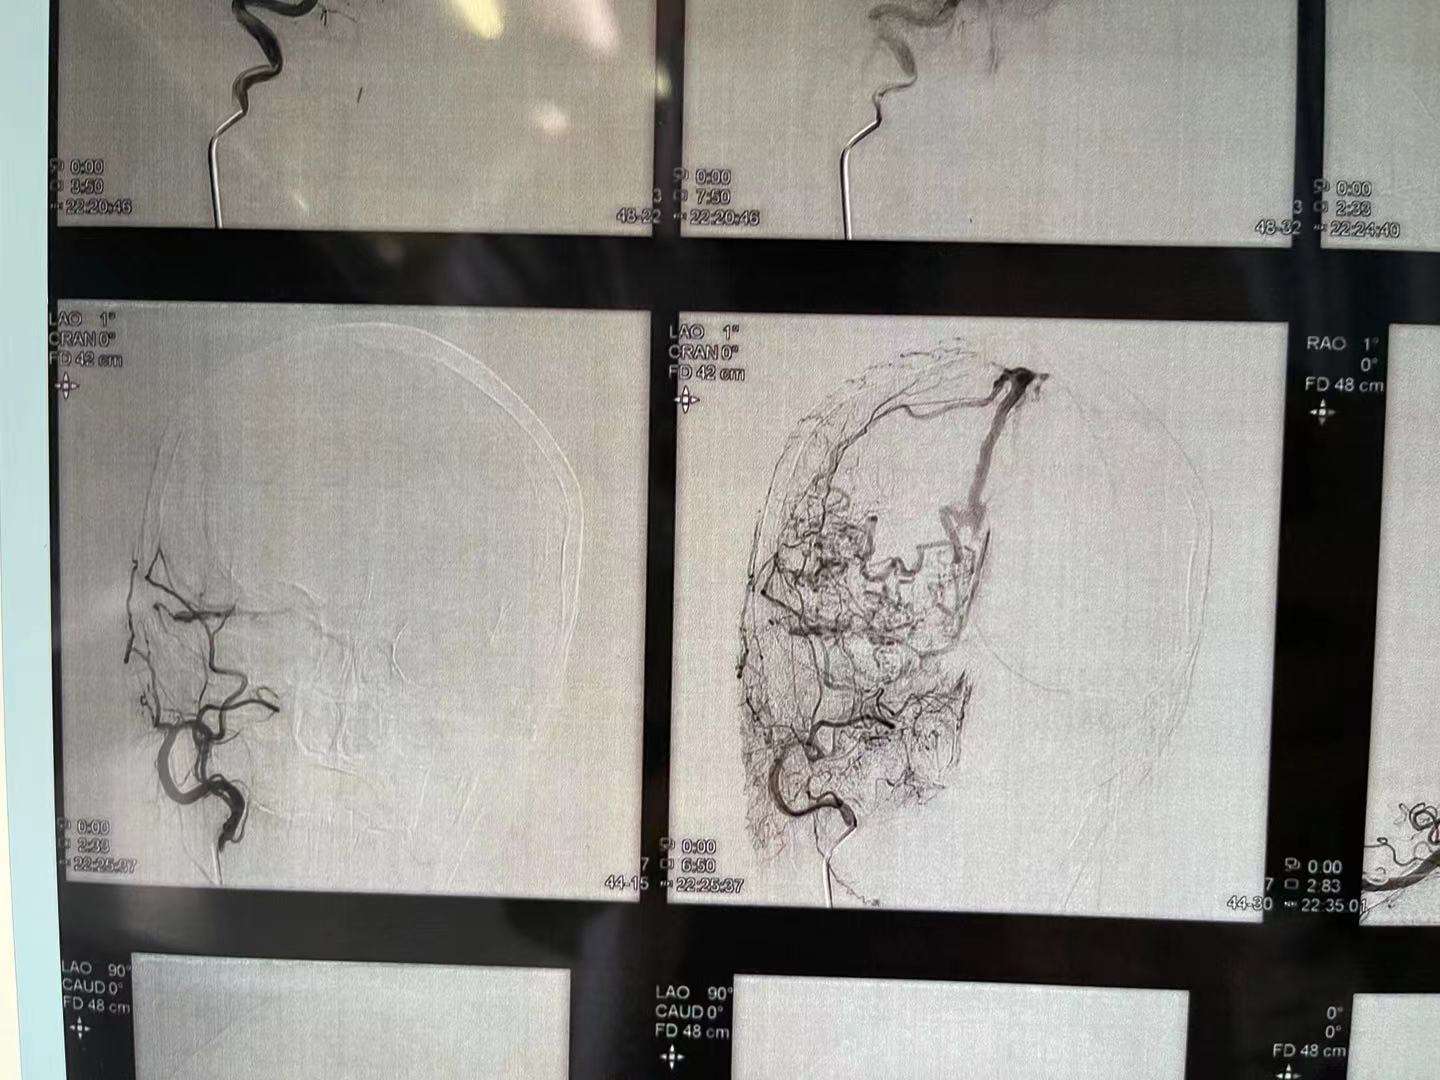

患者女性,68岁,头痛入院,行造影检查硬脑膜动静脉瘘,双侧脑膜中及枕动脉主要供血,开口位于枕部,皮层引流静脉代偿性粗大,拟介入栓塞

看看术前造影,迂曲的静脉,上矢状窦后三分之一及横窦已经不显影了

患者女性,68岁,头痛入院,行造影检查硬脑膜动静脉瘘,双侧脑膜中及枕动脉主要供血,开口位于枕部,皮层引流静脉代偿性粗大,拟介入栓塞

看看术前造影,迂曲的静脉,上矢状窦后三分之一及横窦已经不显影了